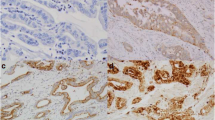

Immunohistochemical analysis of claudin-2 in normal kidney (as a control) as well as in GC and CRC tissues. Staining for claudin-2 was observed in the basal membranes of the proximal tubule of the kidney (a), the cellular membrane of GC cells forming a tubular structure (b), and the cellular membrane of CRC cells forming a papillotubular structure (c). c is case number 1, which expressed claudin-2 at a high level (more than 5 arbitrary units measured by quantitative RT-PCR), as shown in Fig. 3a,b. Original magnification was ×400

We then examined the expression of claudin-2 protein in 146 GC and 99 CRC samples by immunohistochemistry. Immunostaining was also performed in normal kidney to serve as a positive control because our real-time RT-PCR revealed a high expression level and a previous report showed claudin-2 expression in mouse nephron. In the kidney, claudin-2 positivity was found strongest in the basal membranes of the proximal tubule, which is consistent with the result of previous reports [3, 9] (Fig. 3a). No obvious staining of claudin-2 was found in normal liver, stomach, and small and large intestines (data not shown). Of the 146 cases of GC, only 3 (2.1%) were positive for claudin-2. Immunoreactivity of claudin-2 was mainly observed in the cell membranes of GC cells forming a tubular structure (Fig. 3b). In CRCs, 25 (25.3%) of 99 cases were positive for claudin-2. Claudin-2 was mainly localized in the cell membranes of tumor cells forming a papillotubular structure (Fig. 3c).